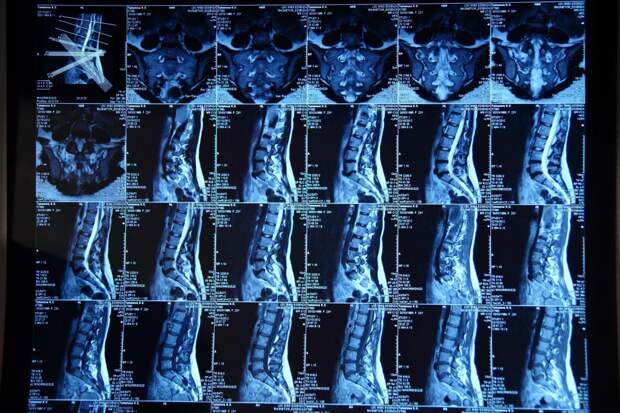

Снимки МРТ позвоночника

Спинной отдел человеческого тела состоит из сложноструктурных сегментов, каждый из которых может быть детально изучен с помощью магнитно-резонансной томографии. Для точного и глубокого анализа проводят разные виды сканирования, доступные в медицинских центрах с высокопольными томографами.

Обследование проводится в стандартной форме и с введением контрастного вещества, которое помогает детализировать визуализацию воспалительных процессов, защемления нервных окончаний или сосудистых аномалий, а также определить наличие новообразований. Процесс сканирования стандартен, однако при применении контраста нужна подготовка и времени на распределение препарата по организму. Методики отличаются уровнем детализации получаемых изображений.